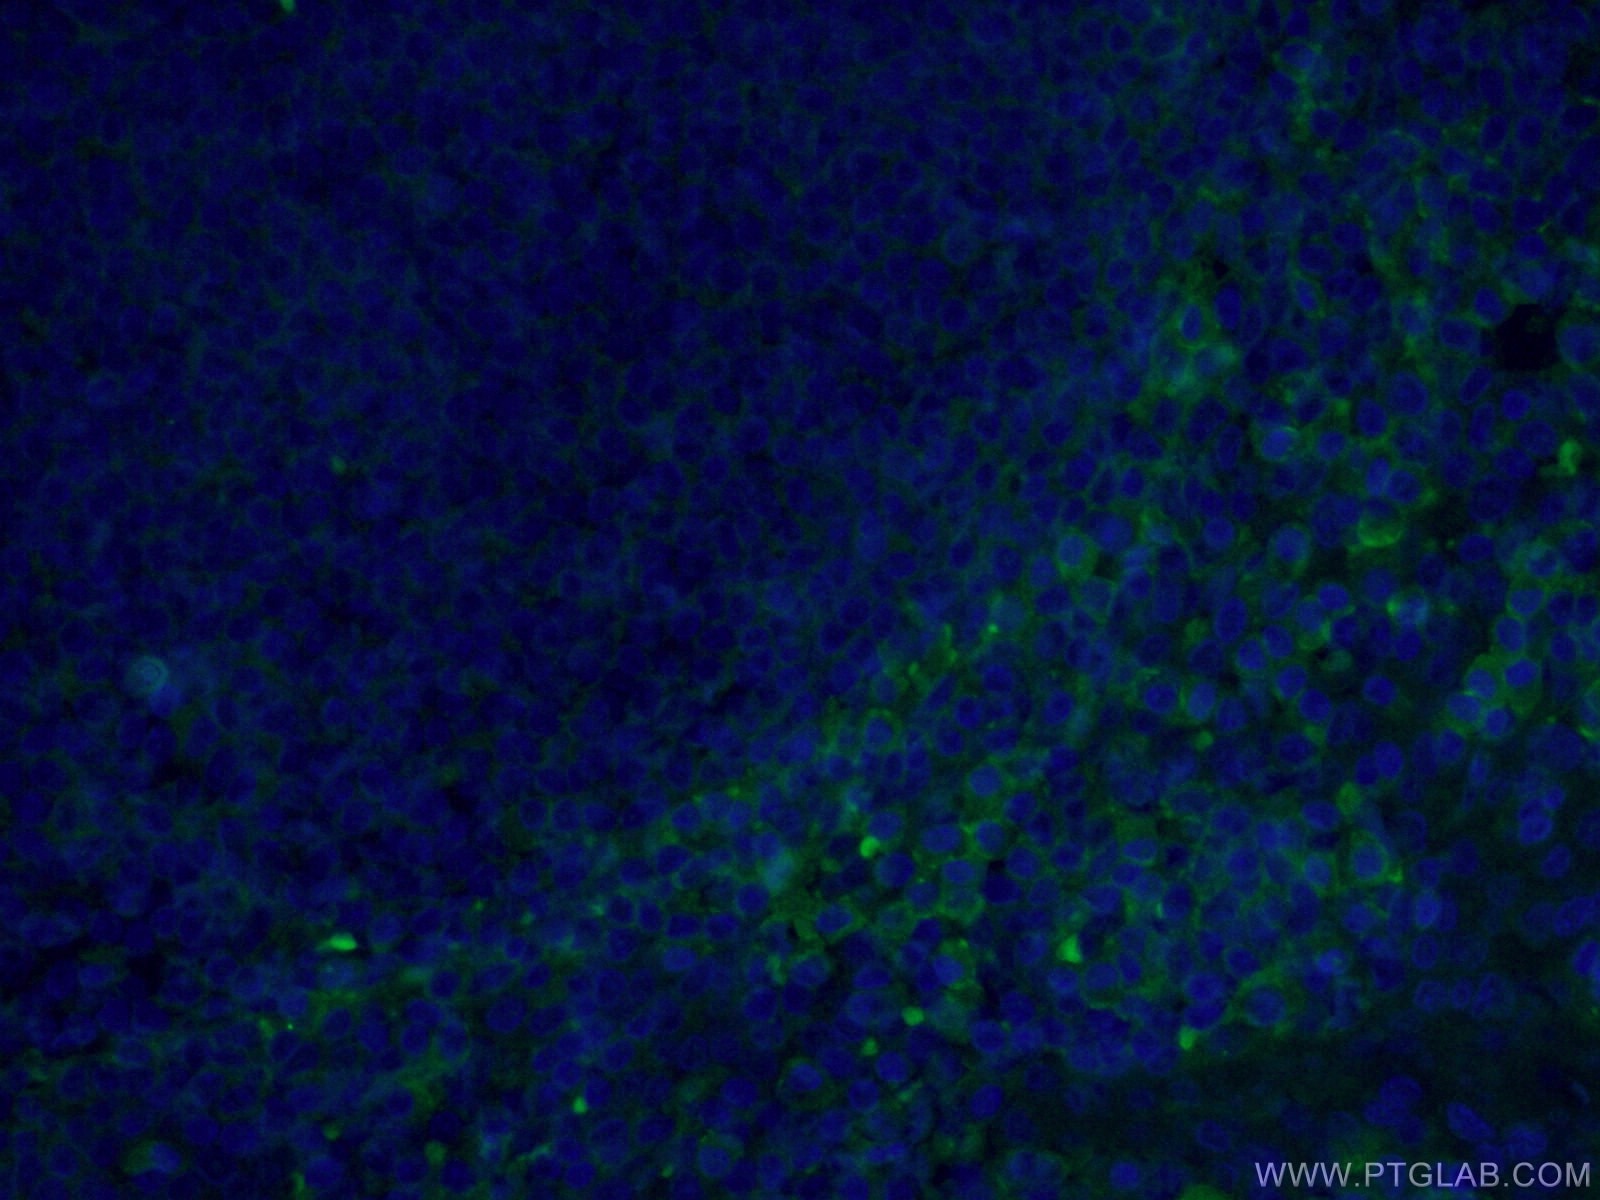

-This figure shows a positive case of CD47 expression analysis. Dot | Download Scientific Diagram cd4487